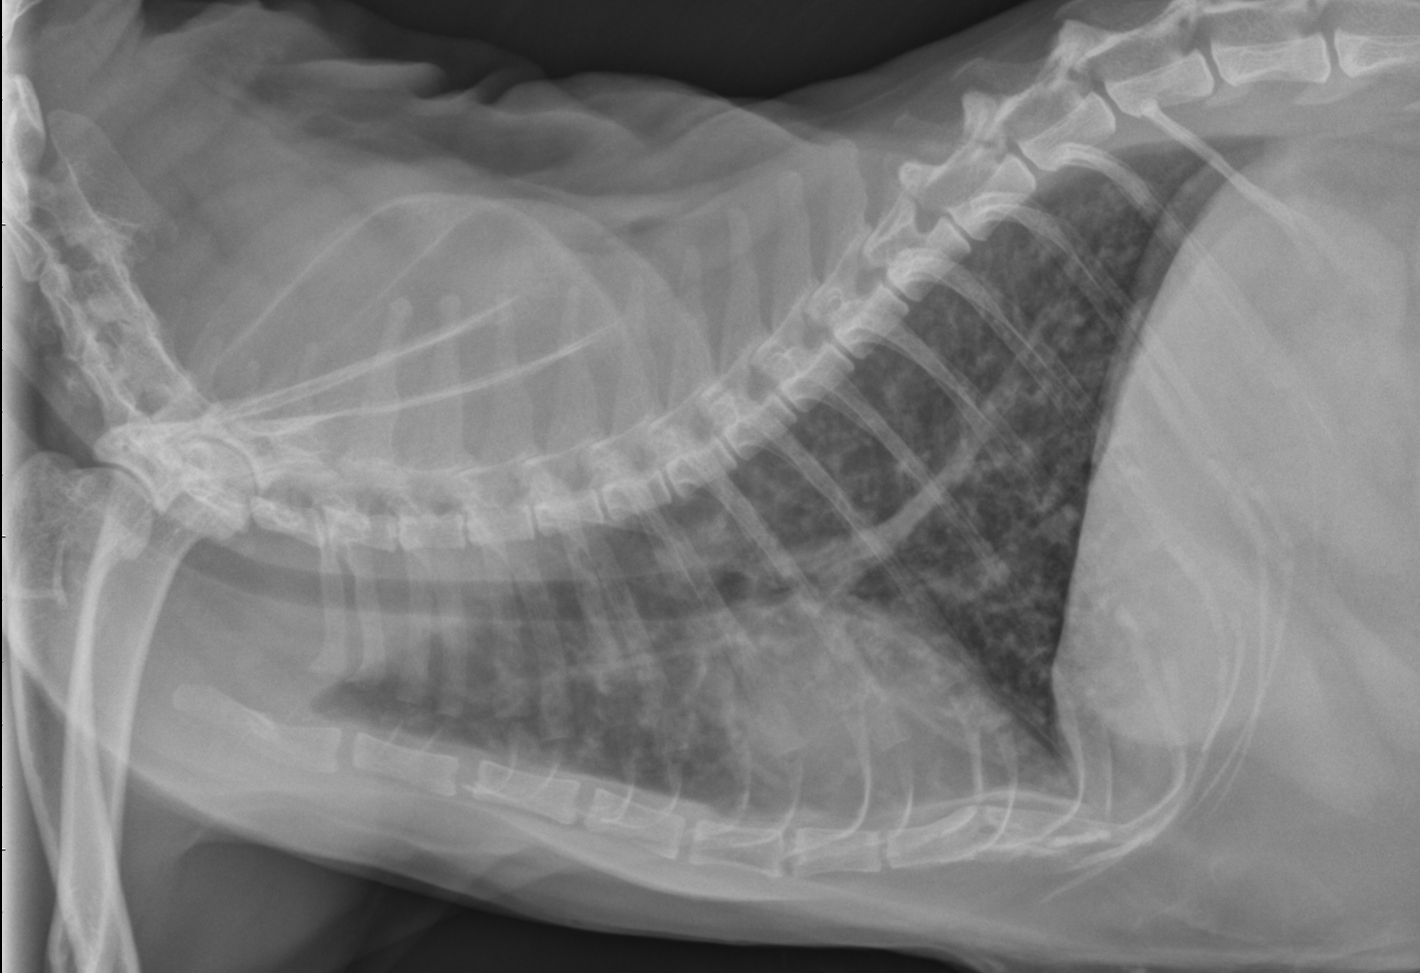

Radiographie patte chaton

Radiographie patte chaton-Un chat retombe toujours sur ses pattes, si la hauteur est suffisante pour qu'il se retourne Malgré cela, il arrive des accidents, et souvent avec des voitures Ce peut être aussi une chute qui n'a pas pu être maîtrisée Si à la suite d'un accident, votre chat s'est fracturé un membre, voici comment vous devez agir Poser le diagnostic Si votre chat ne fait que boîter, il peutUne perturbation des nerfs peut affecter presque n'importe quelle partie du corps de votre chat comme son visage, sa bouche, ses pattes ou sa queue Et comme le système nerveux affecte la plupart des principales fonctions corporelles de votre chat, des problèmes d'équilibre, d'élocution (miaulement), d'alimentation et de défécation peuvent également être présents s'il a un

Radiographie de la fracture de la patte des chats Radiographie de la patte cassée d'un chatLe bassin étant un cadre, une fracture unique est peu probable L'animal présente généralement au moins deux fractures du bassinConjointement avec l'examen clinique, le vétérinaire regarde la mobilité du chat et examine la patte qui boite Il faut déceler la douleur, le gonflement, une mobilité anormale et des craquements (si la patte « craque » quand on la manipule) À l'aide d'un examen radiologique , on peut déterminer si la patte est cassée et voir la position des os

Rayon X De La Fracture De La Patte Du Chat Radiographie De La Patte Cassee D Un Chat Image Stock Image Du Medecine Anatomie